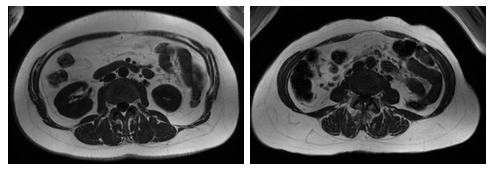

weight and waist circumference can show largely different amounts

of visceral fat vs. fat under the skin in the abdomen